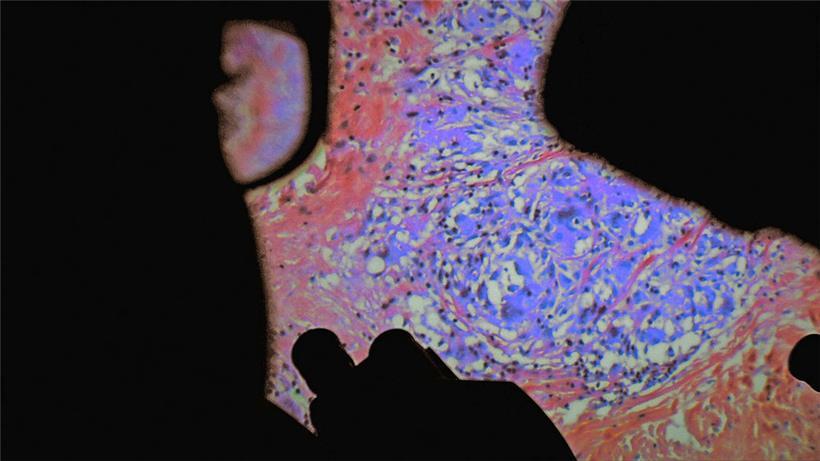

Nicht des Kinos wegen natürlich, sondern aus vorerst medizinischen Ursachen. Paravel und Castaing-Taylor besuchten über eine längere Zeit eine Handvoll Pariser Krankenhäuser und schauten den Ärzten über die Schulter. Tatsächlich präsentieren die beiden vor allem Bilder aus Operationssälen, die man so nicht aus der gewöhnlichen Nachmittags-Ärzteserie kennt. Nein, es sind Bilder, die man so überhaupt noch nicht gesehen hat. Es komme doch immer nur auf die inneren Werte an, haben sie gesagt. Was für die ÄrztInnen Alltagsbilder sind, sind für den Normalsterblichen Bilder, die entweder zuerst gar nicht zu situieren sind, also im Körper – und die dann, in Ermangelung eines besseren Begriffs, schockieren. Schockieren können.

Um sich noch einer weiteren journalistischen Plattitüde zunutzen zu machen – die Regisseure lassen ihr Publikum in eine Welt eintauchen, die plötzlich unergründet und von noch nie gesehener Schönheit strotzt. Ob jetzt in einem Augapfel oder irgendwo in der Bauchgegend operiert wird, Leichen in der Leichenhalle präpariert werden, ein Kaiserschnitt vollzogen oder eine Amputation gezeigt wird, die Regeln des Naturalismus werden bei diesen Bildern außer Kraft gesetzt und metamorphosieren zum Teil zu abstraktem und vor allem experimentellem Bildmaterial, auf das ein Stan Brakhage abfahren würde.